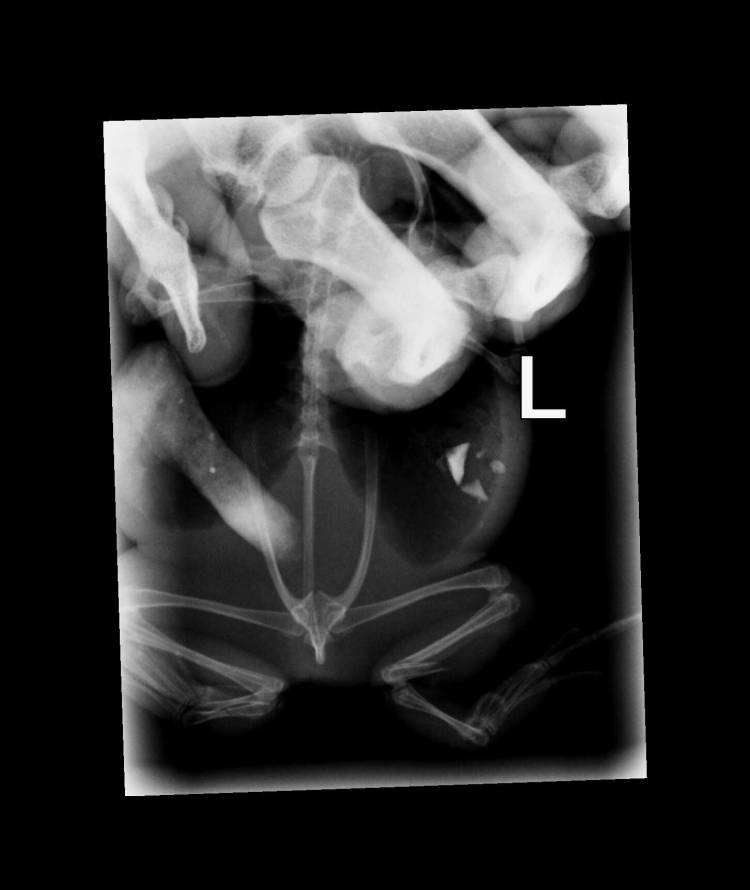

See the X-rays of the toad and read the incredible story of one person going above and beyond to do the right thing.

She had a broken leg and dislocated wrist and the vet was not hopeful.